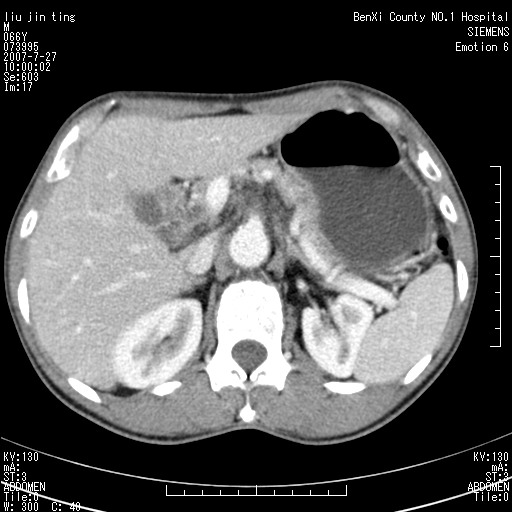

腹痛,背痛,无恶心呕吐,不黄,彩超示胰腺钩癌,ct扫描病灶平扫30-40hu,增强后动脉期40--60hu,静脉期50-68hu,真的是钩突上的么?您要试一试么?

沿着肠系膜上动脉呈匍匐性生长的软组织肿块,形态不规则,包绕肠系膜上动脉,呈明显强化,考虑来源于肠系膜的恶性肿瘤

沿着肠系膜上动脉呈匍匐性生长的软组织肿块,形态不规则,包绕肠系膜上动脉,呈轻-中度强化,考虑来源于肠系膜的恶性肿瘤。

钩突是正常的,只见腹膜后淋巴结的肿大,考虑淋巴瘤或转移可能。

支持!恶性纤维组织细胞瘤可能,与淋巴瘤及淋巴结转移鉴别(腹主动脉周围清晰,其他部位亦未见明显肿大淋巴结)。